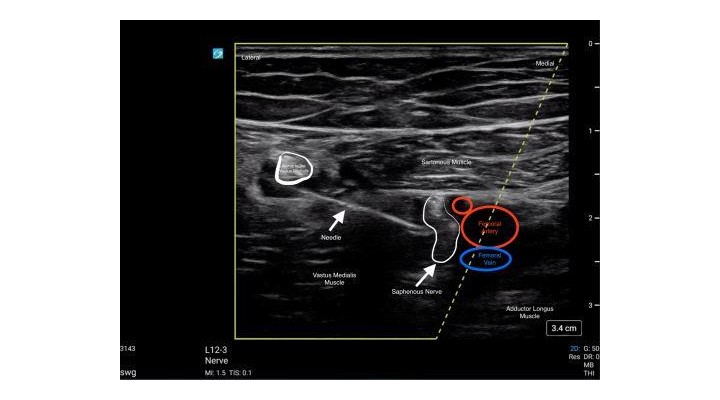

- Identify the Femoral Artery and Vein within the Adductor Canal formed by the Sartorious Muscle (anterior wall), the Vastus Medialis (lateral wall) and the Adductor Longus (medial wall). The Saphenous Nerve is sometimes visualized within the canal.

- Use an in-plane lateral to medial approach with the block needle. The initial injection should occur lateral to the Femoral Artery within the Adductor Canal.

- In addition to injection of local anesthetic lateral to the femoral artery, it may be beneficial to inject local anesthetic medial to the femoral artery via hydrodissection between the Sartorious muscle and Femoral Artery. This may ensure a more complete consistent block.

- The Nerve to the Vastus Medialis may be visualized lateral to the Adductor Canal. Care should be used to avoid injury to this nerve with the block needle on approach to the Adductor Canal. You may choose to block this nerve if visualized.